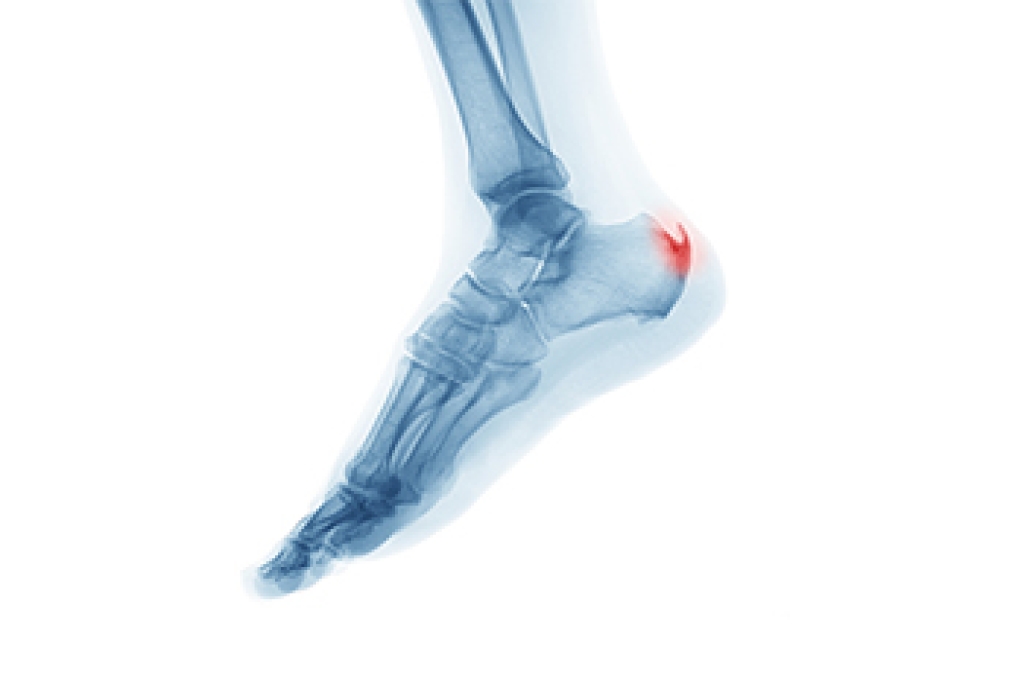

What Is Plantar Fasciitis?

Plantar fasciitis is the inflammation of the thick band of tissue that runs along the bottom of your foot, known as the plantar fascia, and causes mild to severe heel pain.